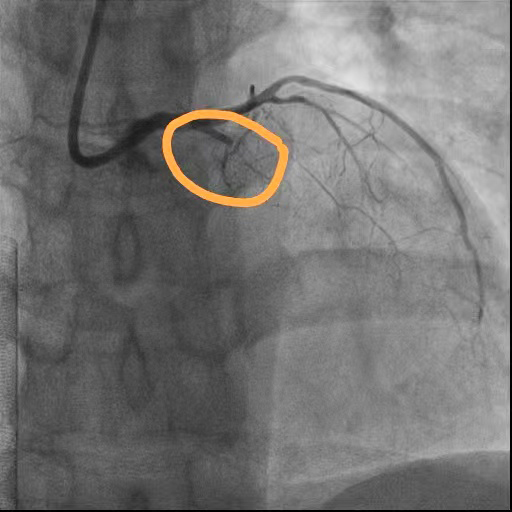

术前

回旋支狭窄

前降支近段闭塞